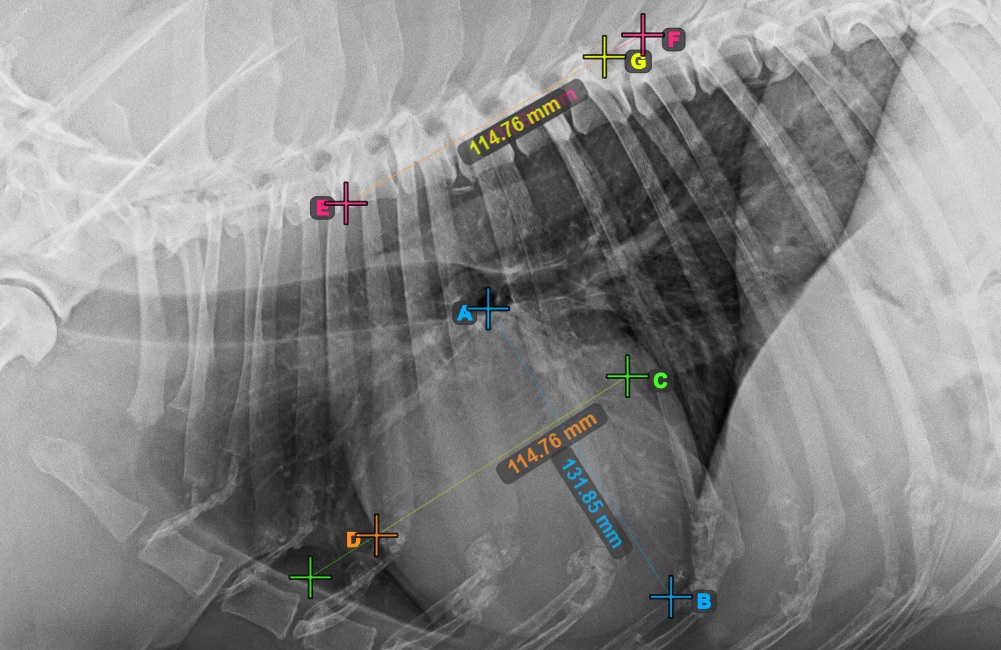

VHS (Vertebral Heart Score) is a measurement used in veterinary medicine to assess the size and health of the patient’s heart. Select the VHS Measurement from the Advanced Measurement menu and assign the left mouse button to it.

The VHS measurement uses the size of the heart in comparison to the vertebrae in the spine to determine and indicate cardiac abnormalities in patients.

Start the measurement by marking the Bifurcatio tracheae, near the top of the heart.

The image below represents a typical placement of the Bifurcatio tracheae point.

Complete the long axis of the heart by marking the Apex point, near the bottom of the heart.

The image below represents a typical placement of the Apex point.

Continue the measurement by marking the widest right (cranial) point of the short axis of the heart.

The image below represents a typical placement of the most cranial point on the short axis of the heart.

Complete the short axis of the heart by marking the widest left (caudal) point.

The image below represents the typical placement of the most caudal point on the short axis of the heart.

Identify the beginning of the T4 vertebra (the fourth vertebral body of the spine), counting from the initial point of the spine. Mark the beginning of the T4 vertebrae to continue the measurement. The software will draw lines from the marked point along the spine. The length of the lines depends on the measured long and short axes of the heart.

The image below represents the typical placement of the point at the beginning of the fourth vertebral body of the spine.

Before proceeding with the required VHS calculations, make sure that the lines are placed precisely along the vertebrae.

Count the number of vertebrae along the line representing the short axis on the spine. Specify the required vertebrae count in the Vertebrae Count input field in the advanced measurement mode toolbar.

Press Calculate VHS Score to perform the required calculations for the VHS measurement. The VHS score will be shown in the advanced measurement mode toolbar. Additionally, the VHS score will be labeled on the image, as part of the measurement.